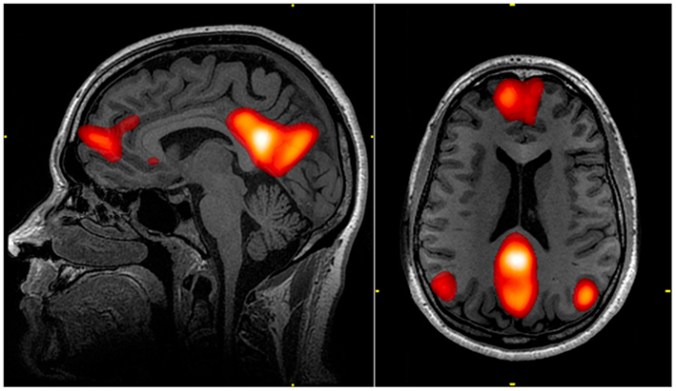

In recent years, the search for the underlying causes of depression have focused on the Default Mode Network (DMN), a system in the brain that is a core aspect of our consciousness and sense of self. When you are remembering the past, daydreaming, or thinking about yourself or others, the DMN is active. The DMN is found to be overactive in patients with major depression, perhaps causing the negative thoughts and ruminations associated with depression 3.

MRI scan showing the brain regions that make up the Default Mode Network. Image from Graner et al. (2013) 8.

Two of the studies recently released by Prof Nutt’s group suggest that the classic psychedelics LSD and psilocybin may be antidepressive, through their interactions with the DMN. The first of these studies uses the natural psychedelic psilocybin (click here to learn more about psilocybin). Carhart-Harris’ group had previously discovered that psilocybin reduces the activity of the DMN 4, prompting them to investigate psilocybin and depression.

The second study addresses LSD (click here to find out more about LSD), a synthetic psychedelic drug that works in a similar manner to psilocybin. For the first time ever, Prof Nutt’s group performed multiple neuroimaging experiments on patients that were given LSD 6. The results are complex and extensive, but one of the most interesting findings concerned the DMN. Nutt’s group discovered that LSD reduced the activity of the DMN, and that this was associated with ‘ego dissolution’ in the patients. This means that patients lost their sense of self and became less focussed on the typical worries of everyday life. This evidence supports the idea that classical psychedelics may be a unique tool in the treatment of depression, through their actions on the DMN.